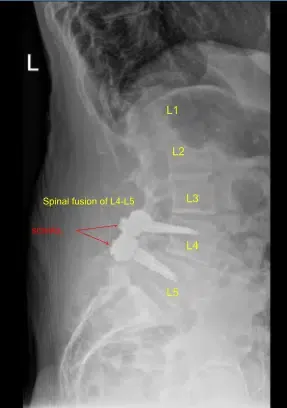

Spinal Fusion of L4-L5

Prior physical examination of the lumbar spine supported the diagnosis of lumbar canal stenosis. His imaging showed grade 1 to grade 2 spondylolisthesis with instability over L4-L5 with compression of nerve roots. There is also lateral recess compression at L3-L4 on the right and left side with compression of the traversing L4 nerve root.